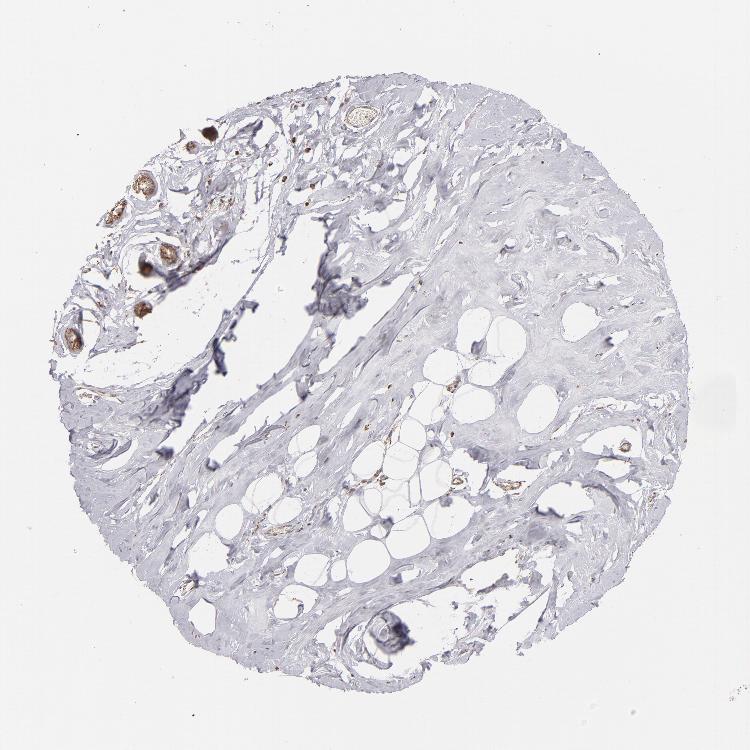

SOD2